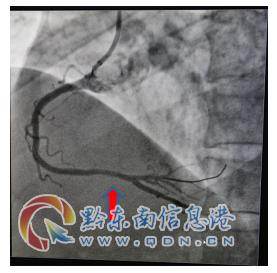

該患者入院查肌鈣蛋白、心肌酶增高,復查心電圖提示“Q波加深、ST段下移較前明顯”,結合輔助檢查結果陳文海主任對患者病情診斷為急性心肌梗死,考慮患者合并有糖尿病、甲亢等多種病癥,病情緊急,需按照胸痛中心急性心肌梗死流程緊急處理。經過該院心血管內科專家的會診評估,認為及早行冠脈介入診療對患者是有益的。征得該患者及家屬的同意后,立即啟動導管室行冠脈造影檢查,造影提示右冠脈遠段重度狹窄病變,在李健民副主任醫師的指導下,心血管內科陳文海主任、楊文林醫師對患者繼續行藥物球囊擴張術,選擇支架植入為補救治療方案。冠脈介入過程謹慎細致,最后判斷冠脈藥物球囊擴張術對患者獲益更大后,予以藥物球囊擴張術,不需植入冠脈支架,造影復查嚴重狹窄病變處經藥物球囊擴張術處理后,殘余狹窄小于30%,達到治療效果。手術過程歷經不足半小時,成功開通狹窄病變的冠脈血管,TIMI血流3級,手術效果滿意,術后患者安返病房,未再出現胸痛癥狀。

術后藥物球囊擴張后